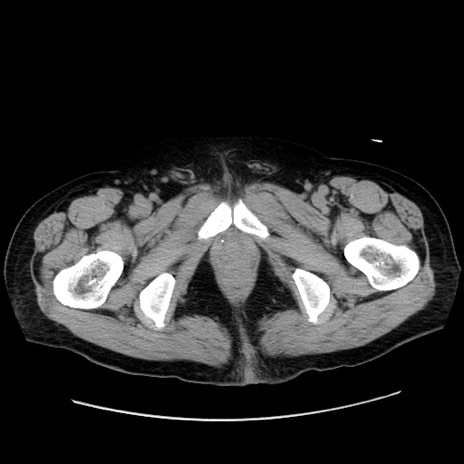

冠状断像

【症例】80歳代男性

【現病歴】約6時間前から臍下部痛が出現。次第に腹部膨隆・背部痛も生じてきたため来院。背部痛の場所は変化しない。

【身体所見】意識清明、BT 36.3℃、BP  131/87mmHg、P 87bpm、SpO2 100%(RA)、臍周囲自発痛・圧痛あり、反跳痛なし、自発痛部位に一致して板状硬あり、腹部膨隆、腸雑音減弱、CVA tenderness両側陰性。